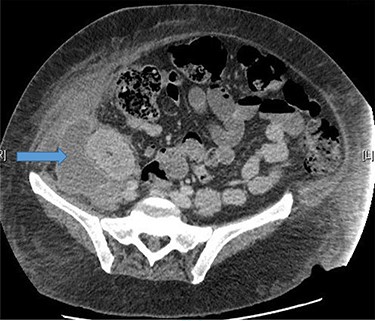

A 48-year-old lady was admitted from the outpatient surgical clinic with a painful lump in the right iliac fossa for a duration of 4 weeks. The patient had undergone kidney autotransplantation long time ago and she had a rooftop incision over the overlying kidneys. Patient’s initial diagnostic impression was a query painful obstructed incisional hernia as a result of the previous renal surgery to denervate the nerves and re-implant the kidneys to a different location within the abdominal cavity. In order to confirm the diagnosis, a computed tomography (CT)-abdomen and pelvis with IV contrast was organized. The scan showed a large retroperitoneal loculated collection with tracking of fluid into the anterior abdominal wall, where there were tiny gas pockets close to the anterior margin (Figs 1 and 2). The patient was transfused with three units of packed red cells, given the impression of a chronic hematoma as per the CT scan. Our patient had undergone bilateral autotransplanted kidneys in the iliac fossa region.

Large right retroperitoneal loculated fluid collection superior to the right pelvic kidney with no internal gaseous contents.